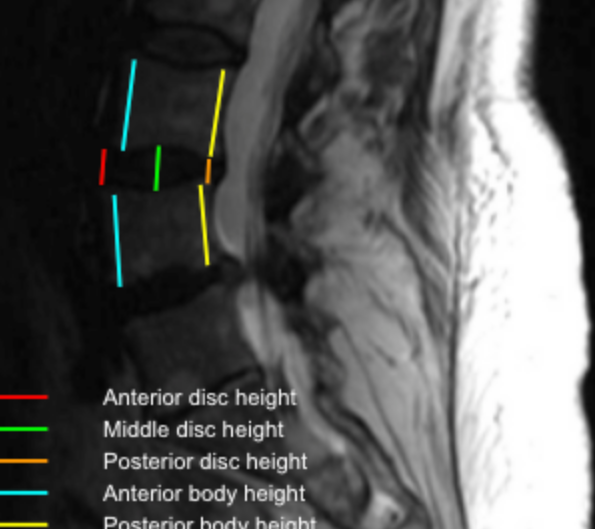

Image Type Lumbar Spine X-Ray CT Scan MRI Scan Anteroposterior (AP) Canal Diameter Cauda Equina Nerve Root Area Conus Medullaris Level Cross-Sectional Area (CSA) of Spinal Canal Disc-Height Index (DHI) Disc Herniation Size Disc Herniation Types Dural Sac CSA Epidural Fat Thickness Filum Terminale Thickness Foraminal Height and Width High-intensity Zone (HIZ) Lateral Recess Width/Depth Modic Endplate Changes (Type I, II, III) Modic (Marrow Signal) Changes Pfirrmann Classification (I-V) Vertebral Bone Quality (VBQ) Score Vertebral Endplate Defects